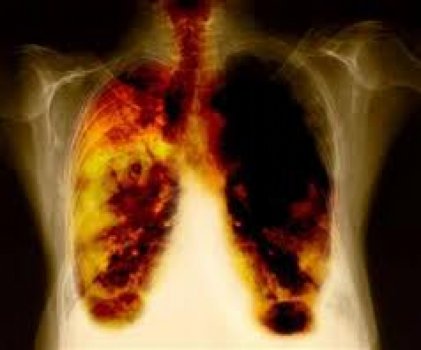

pulm__o_fumante.jpgO FDA aprovou no dia 12 de dezembro o uso do ramucirumabe (Cyramza®) para o tratamento de pacientes com câncer de pulmão não-pequenas células metastático (CPNPC). Esta é a terceira indicação do ramucirumabe recebida pelo FDA em 2014. Em abril, a agência norte-americana aprovou o medicamento para tratar pacientes com câncer de estômago avançado ou adenocarcinoma de junção gastroesofágica (GEJ). Em 5 de novembro, expandiu o uso da droga em associação com paclitaxel para esse perfil de pacientes. Agora, Cyramza® recebe indicação para o tratamento de CPNPC na combinação com docetaxel.